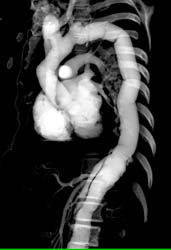

Diagnosis

Large Endoleak